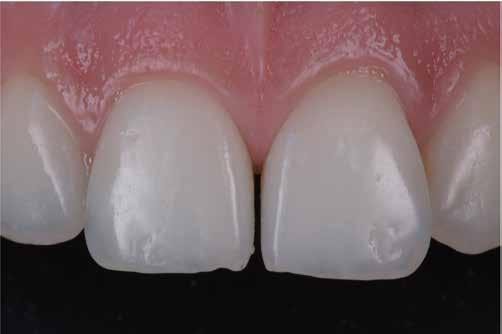

Nem volt kedvencem, de kevésbé kedveltem a hibrid technikát, ahol a palatális fal wax-uppal történő felépítése, majd a nyaki terület szabadkézi megerősítése után a restauráció többi részét mátrixszal lehetett kivitelezni (1. ábra). Bár a kezemben ez valahogy hatékony volt, mégis bonyolult volt.

1. ábra: A wax-up alapú technikák gyakori problémái, a szájpadlásfal apikális része hibás.

2-4. ábra: Gyakori problémák klasszikus megközelítéssel. 5. ábra: Tökéletes vészhelyzeti profil elülső szárnyas technikával. Dr. Jun Iwata, Japán jóvoltából.